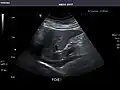

Spleen -